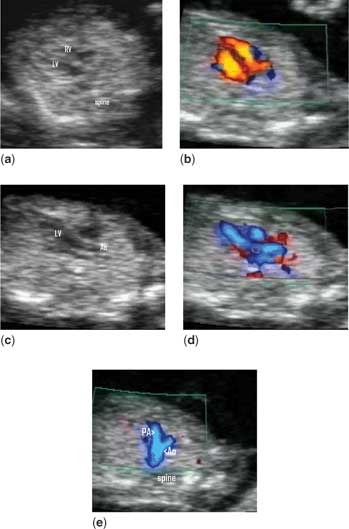

The rate of congenital cardiac disease increases concomitant with the increase in nuchal translucency. When the nuchal translucency is between 2.5millimetres and 3.5 millimetres, the rate is 2%, over twice the normal rate. Between 3.5 millimetres and 4.5 millimetres, it is 4%, between 4.5 millimetres and 5.5 millimetres, 6.5%, between 5.5 millimetres and 6.5 millimetres, 14%, and over 6.5 millimetres, it rises to 26%.16 Those patients with an increased nuchal translucency now constitute the most important group of our current referrals for fetal echocardiography deemed to be at high risk, yielding one-third of our fetal cardiac anomalies. Our policy is to scan the fetus at the time of detection of a nuchal translucency above 3.5 millimetres, therefore between 11 and 14 weeks of gestation. For those patients with a nuchal translucency between 2.5 millimetres and 3.5 millimetres, detailed fetal echocardiography is scheduled instead for 20 weeks. In a series of 1210 fetuses seen between 11 and 14 weeks since 2000, 980 had a nuchal translucency over 3.5 millimetres, the rest forming a normal control group. Diagnostic images were obtained abdominally in nine-tenths of cases. Of the 980, one-quarter (252) had abnormal cardiac findings, of whom 85% had karyotypic abnormalities. It is important to realise that detailed fetal cardiac evaluation is difficult at 12 weeks, and becomes progressively easier with every day between 12 and 14 weeks. The mean size of the aorta and pulmonary arteries at this gestation is about 1 millimetre, whereas by 14 weeks they are about 1.7 millimetres, and 3.5 millimetres by 20 weeks, so the heart more than triples in size between 12 and 20 weeks. Despite this, with experience and practice, it is usually possible to display clearly two atriums and two ventricles of equal size, two great arteries in spiralling relationship, the arch, and the arterial duct (Fig. 2). Use of colour flow mapping in these tiny chambers and vessels allows confirmation of flow throughout the heart in the expected antegrade fashion. Doppler sampling of the atrioventricular and arterial valves is usually possible. This being true, the failure to demonstrate normal findings is suspicious, and the subsequent recognition of anomalies such as the hypoplastic left heart syndrome, atrioventricular septal defect, pulmonary atresia with intact septum, and discordant ventriculo-arterial connections have all reliably been made in this setting (Figs 3–7). Sometimes during the nuchal scan, the sonographer recognises a cardiac malformation even when the nuchal translucency is normal (Fig. 8), so this screening programme in itself often leads to early referrals. Many fetuses with a diagnosis of congenital cardiac disease, which is associated with a chromosomal defect, proceed to termination of pregnancy. There is often no confirmation of the diagnosis by autopsy. In a fairly large series of patients, however, we have been able to obtain follow-up either by autopsy, in 32 cases, or by later fetal scan, in 218 cases. Of these 250, confirmation of the findings was complete in 243, with only minor revisions or additions to diagnosis made in the remainder.

Figure 2. A normal heart (a) is seen at 12 weeks in the four-chamber view. Two equal atriums and ventricles can be seen, which fill on colour flow mapping (b) across patent atrioventricular valves. The origin of the aorta from the left ventricle can be seen (c), and is confirmed on colour flow mapping (d). In the plane immediately cranial to that shown in (d), the pulmonary trunk can be seen crossing over the aortic origin (e), confirming the normal spiral arrangement of the great arteries and that the vessels are of approximately equal size.